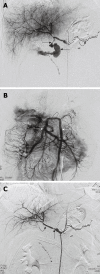

Aim: To present a series of cases with life-threatening hemorrhage from ruptured hepatic artery pseudoaneurysm after pancreaticoduodenectomy (PD) treated with placement of stent-grafts.

Methods: Massive hemorrhage from ruptured hepatic artery pseudoaneurysm after PD in 9 patients (6 men, 3 women) at the age of 23-75 years (mean 48 years), were treated with placement of percutaneous endovascular balloon-expandable coronary stent-grafts. All patients were not suitable for embolization because of a non-patent portal vein. One or more stent-grafts, ranging 3-6 mm in diameter and 16-55 mm in length, were placed to exclude ruptured pseudoaneurysm. Follow-up data, including clinical condition, liver function tests, and Doppler ultrasound examination, were recorded at the outpatient clinic.

Results: Immediate technical success was achieved in all the 9 patients. All stent-grafts were deployed in the intended position for immediate cessation of bleeding and preservation of satisfactory hepatic arterial blood flow. No significant procedure-related complications occurred. Recurrent bleeding occurred in 2 patients at 16 and 24 h, respectively, after placement of stent-grafts and treated with surgical revision. One patient died of sepsis 12 d after the interventional procedure. The remaining 6 patients were survived when they were discharged. The mean follow-up time was 10.5 mo (range 4-16 mo). No patient had recurrent bleeding after discharge. Doppler ultrasound examination verified the patency of hepatic artery and stent-grafts during the follow-up.

Conclusion: Placement of stent-grafts is an effective and safe procedure for acute life-threatening hemorrhage from ruptured hepatic artery pseudoaneurysm.